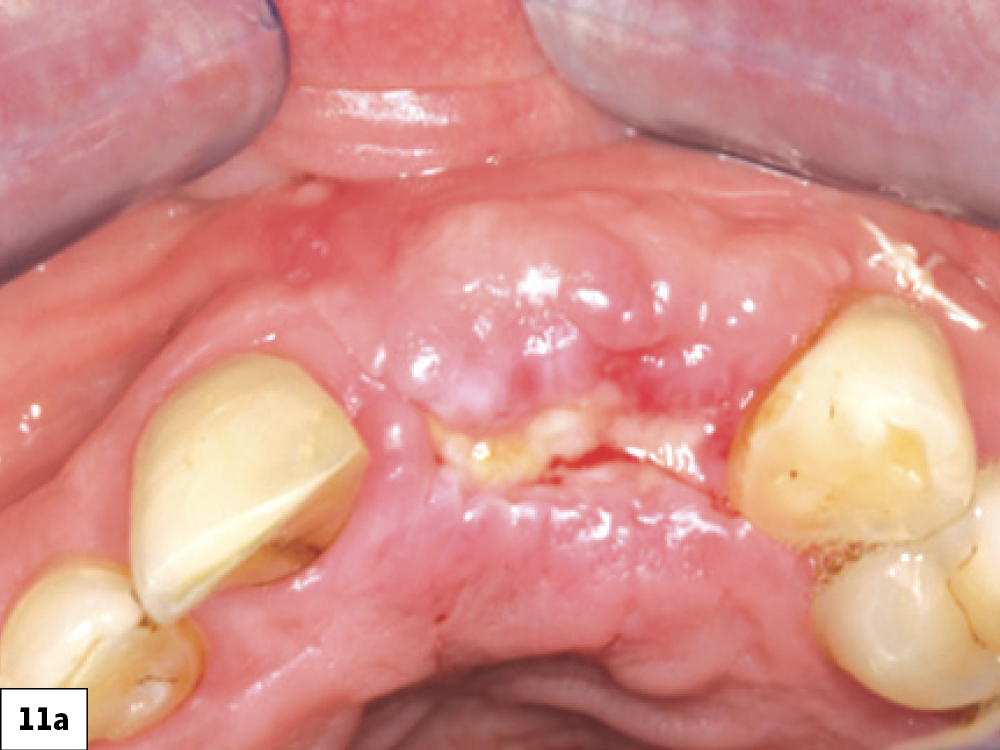

In most ILO cases, the correct treatment is to allow the surgical wound to heal via secondary intention. Allowing the site to heal by secondary intention requires considerable discipline and patient cooperation for a successful outcome (Box 2, Fig. 11). This treatment approach is influenced by various factors such as the health of existing tissue, tissue thickness, location, patient age and the size of the dehiscence. The technique involves implementing the following:

Successful healing by secondary intention: (a) two-week postop with ILO, (b) three-week post-op, (c) successful re-epithelization at four-week post-op.

Figures 11a–11c: Successful healing by secondary intention: (a) two-week post-op with ILO, (b) three-week post-op, (c) successful re-epithelization at four-week post-op.